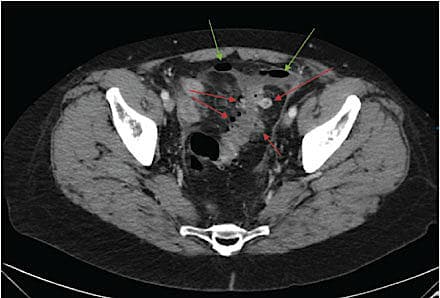

Akut, kompliceret divertikulitis kan inddeles i fire stadier i henhold til Hinchey-klassifikationen, jf. Tabel 1 [1, 3] og udgør en mindre andel af de samlede tilfælde af akut divertikulitis [8]. Med Hinchey-graderingen klassificerer man ud fra peroperative fund og skelner mellem abscesdannelse og placering, abscesruptur og fuld tarmperforation med fækal peritonitis. Perforeret divertikulitis karakteriseres som hhv. Hinchey-grad III ved fund af perforeret bækkenabsces

eller perikolisk absces med purulent peritonitis og

Hinchey-grad IV ved fuld tarmperforation efter divertikelruptur og heraf følgende fækulent peritonitis [1].